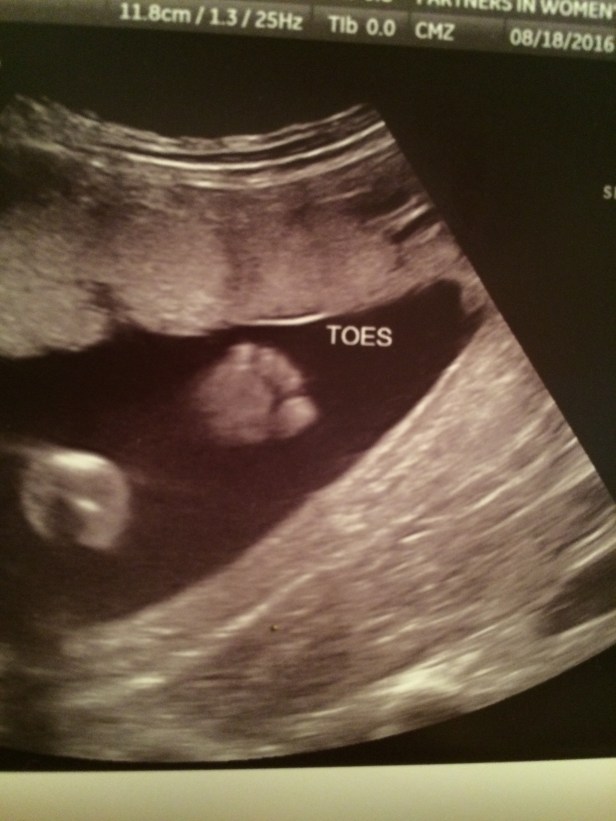

I’ve been meaning to write to you, but it has been difficult to find the words to say so I’ve continued to put it off. In my pain, it was easier not to think about you. As you have grown bigger and stronger, so have your kicks. What started as soft little sensations has turned into more insistent pokes, little reminders that I need to think about and connect with you.

Your life has such a great purpose. The very fact that you are here is a miracle. While your sister was born from months of planning and intention, you were born from a single moment of passion and faith. And a passionate, faith-filled man you will grow up to be. Just like your father.